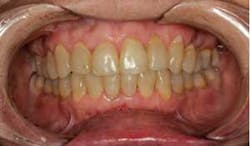

SFOT was used with a high-tech clear aligner to address hard- and soft-tissue deficiencies and severe maxillary and mandibular arch constriction.

A healthy, 57-year-old female presented with a lifelong desire for healthy, straight teeth and a beautiful smile. She had been told numerous times that it was not possible without premolar extractions.

Total treatment time: 6 months. Patient declined recommended further clear aligner refinement and fine-tuning periodontal plastic surgery.